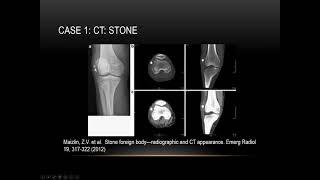

La aplicación presenta más de 300 imágenes de alta calidad, junto con una gama de imágenes de cuentos diseñadas para permitir a los lectores probar y desarrollar sus habilidades de interpretación. Texto sobre la mejora de la rayos X y otras habilidades de interpretación de pruebas de imagen de diagnóstico, para estudiantes y radiólogos.

La aplicación presenta más de 300 imágenes de alta calidad, junto con una Rango de imágenes de la historia de casos diseñadas para permitir a los lectores probar y desarrollar sus habilidades de interpretación.